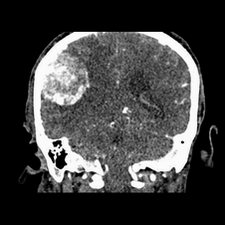

标题: CT25808:男,48岁,头痛多年,近段时间头痛加重伴步态不稳 [打印本页]

标题: CT25808:男,48岁,头痛多年,近段时间头痛加重伴步态不稳

平扫:右颞顶叶病灶呈等低密度伴大面积水肿,脑室受压变形。增强:病灶显著强化。考虑淋巴瘤或黑色素瘤。

1)不排除黑色素瘤可能;建议行mri检查。2)大脑镰下疝。3)脑积水(梗阻性)。